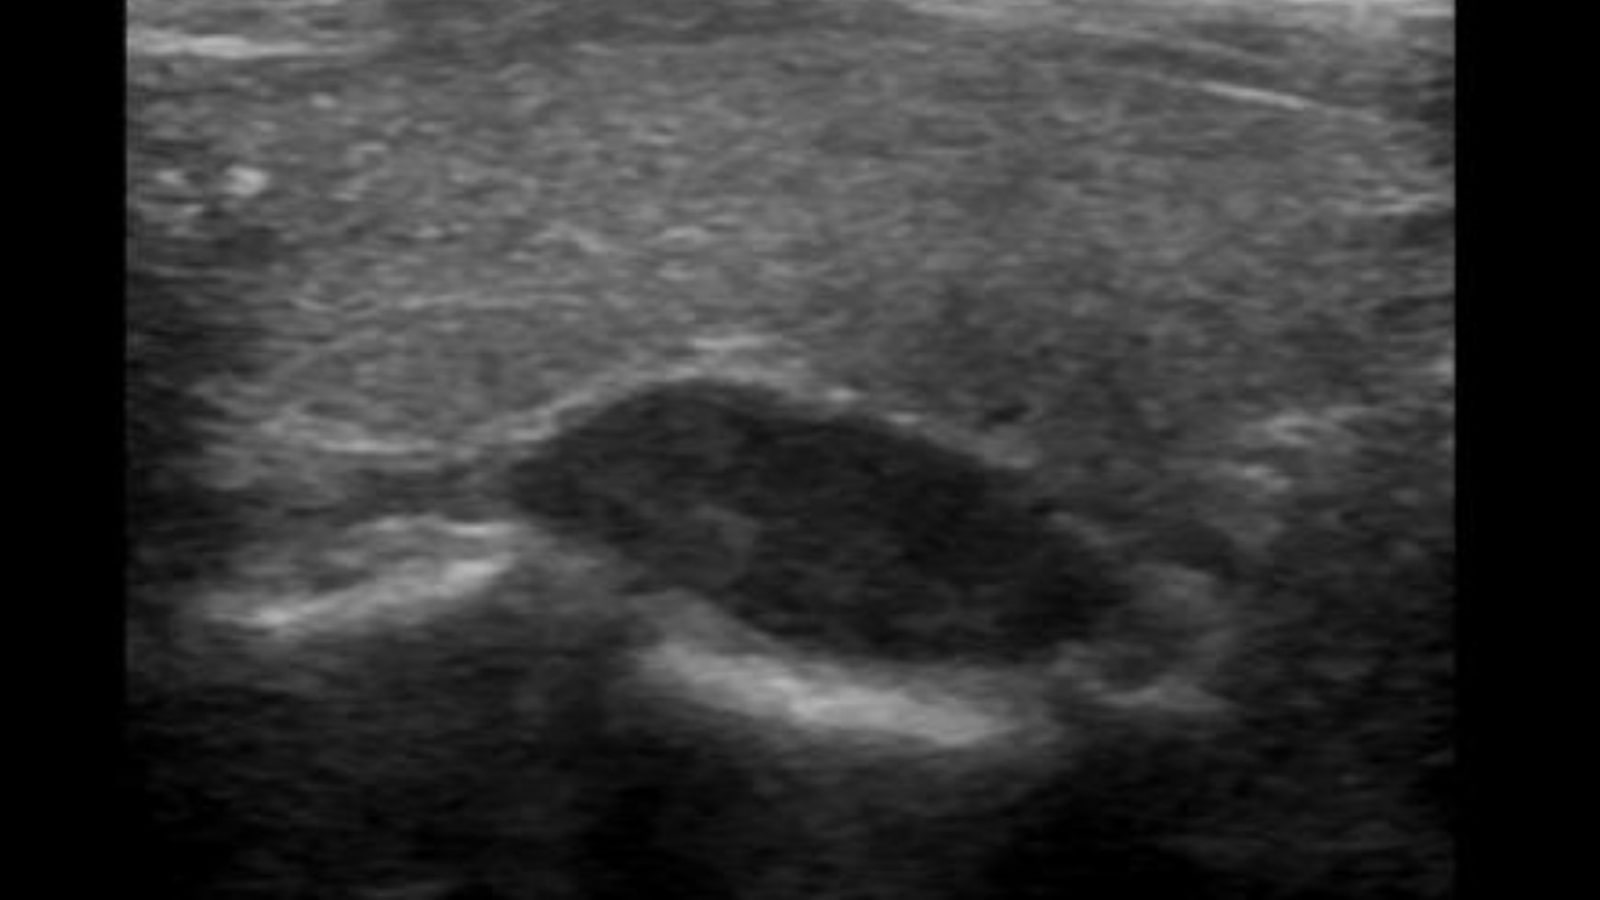

Siêu âm tuyến giáp là phương pháp chẩn đoán hình ảnh chủ yếu, cho phép đánh giá kích thước, vị trí, cấu trúc của khối u. Hệ thống phân loại TI-RADS được sử dụng để đánh giá mức độ nguy cơ ác tính từ 1-5, giúp bác sĩ quyết định có cần sinh thiết hay không.